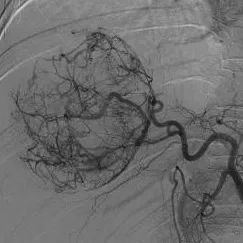

患者被送入导管室后,郑胜与放射科主治医师苏维杰第一时间开始经股动脉肝动脉造影与栓塞术。术中用碘化油及明胶海绵颗粒对出血动脉进行了栓塞,成功止血。

术前